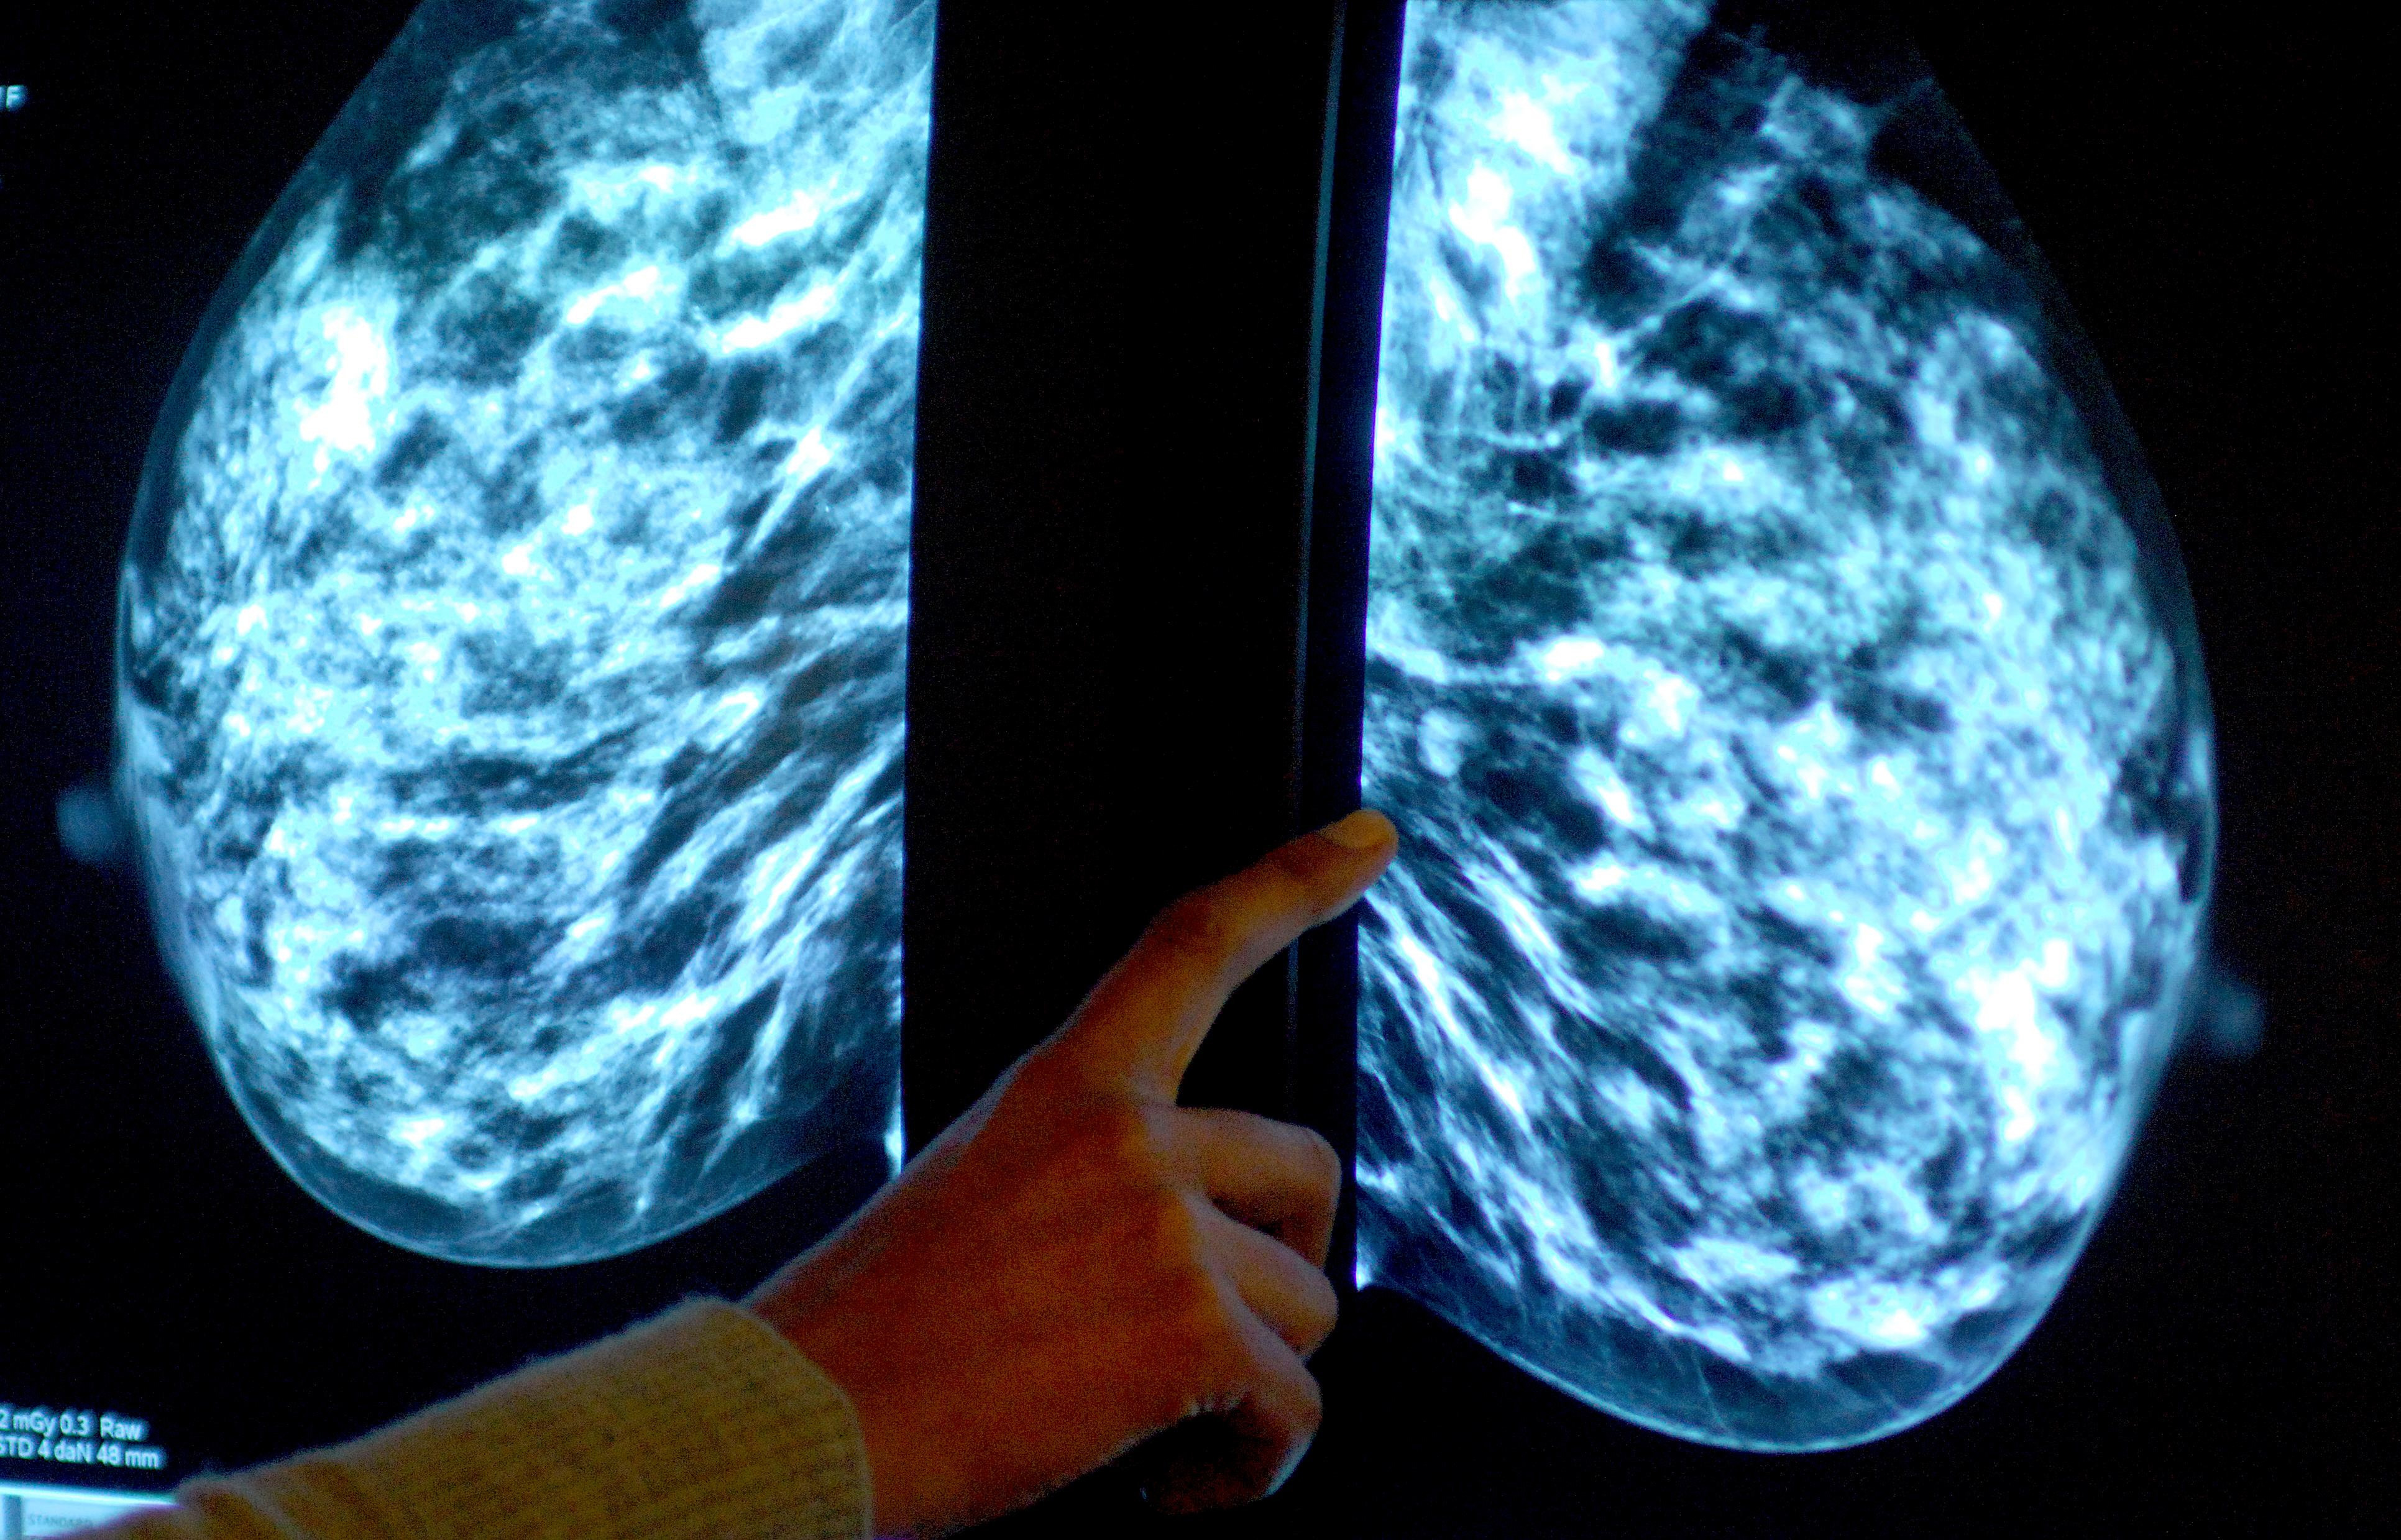

Breast screening uptake in Cornwall remains below pre-pandemic levels, new figures show.

Anyone registered with a GP as female will be invited for NHS breast screening every three years between the ages of 50 and 71.

NHS England figures show 23,810 of the 35,080 people invited for a screening in the former NHS Kernow CCG had a test in the year to March this year.

It meant uptake of the screening stood at 68% – up from 67% the year before, but below pre-pandemic levels of 74% in 2019-20.